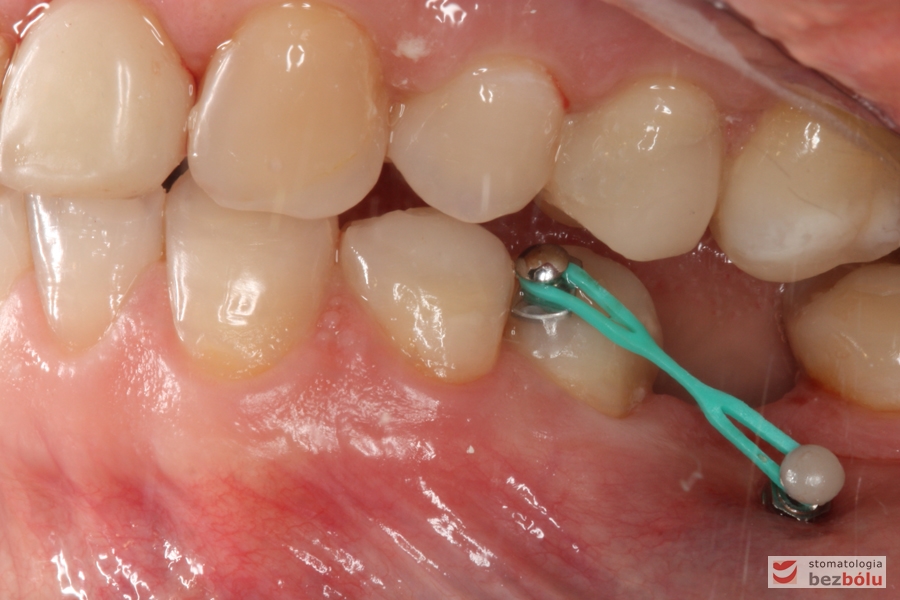

Mikrośruba ortodontyczna - 5 dolna lewa aktywowana do miniimplantu w celu dowargowego wychylenia

Mikrośruba ortodontyczna – 5 dolna lewa aktywowana do miniimplantu w celu dowargowego wychylenia